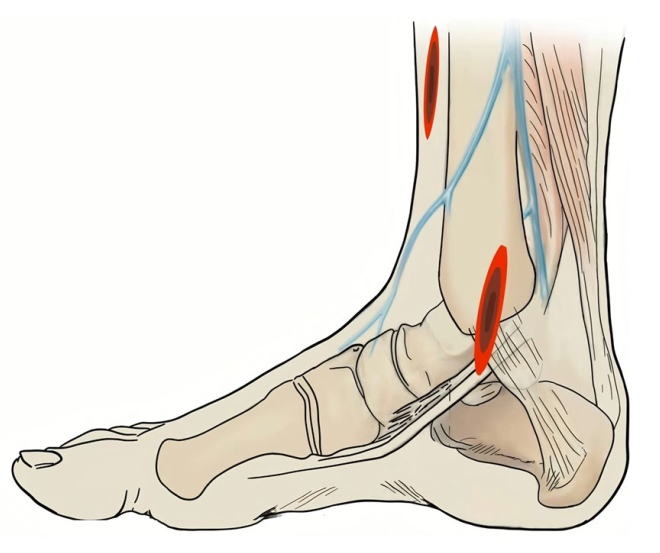

不同于经典的广泛使用的前内侧入路,该方法使用前外侧长切口,自腓骨前缘经外踝至第4跖骨基底,长约15cm。

恢复外踝长度与解剖位置,放置解剖钢板。距骨常向前上方移位,将其下压使其软骨面与外踝内侧平齐;以胫腓骨、距骨正常“奔驰三角”为参照,复位钳维持复位。用2.0mm克氏针临时固定外踝与距骨(避开钢板),以距骨为模板重建胫骨远端关节面。